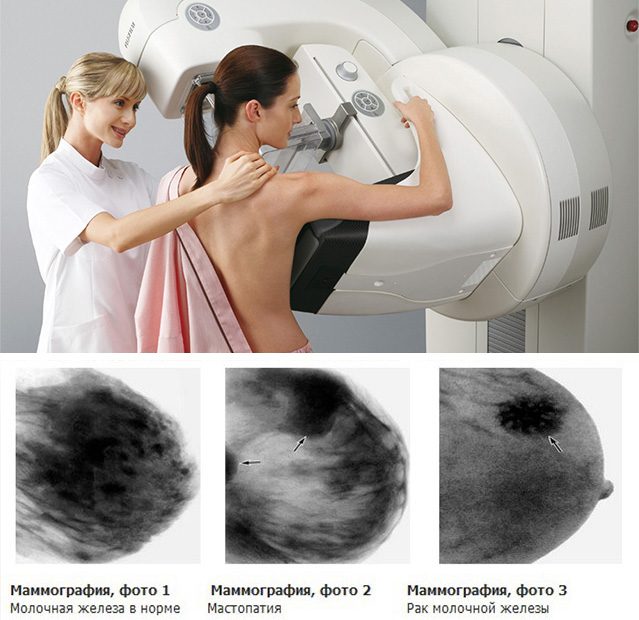

Что такое маммография: важность, процесс и результаты

Раздел: Необычные решения